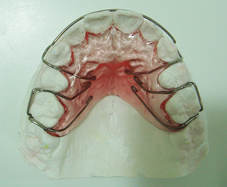

La plaque de Hawley

Elle est réalisée au laboratoire de prothèse au moyen d’une empreinte prise le jour du débaguage.